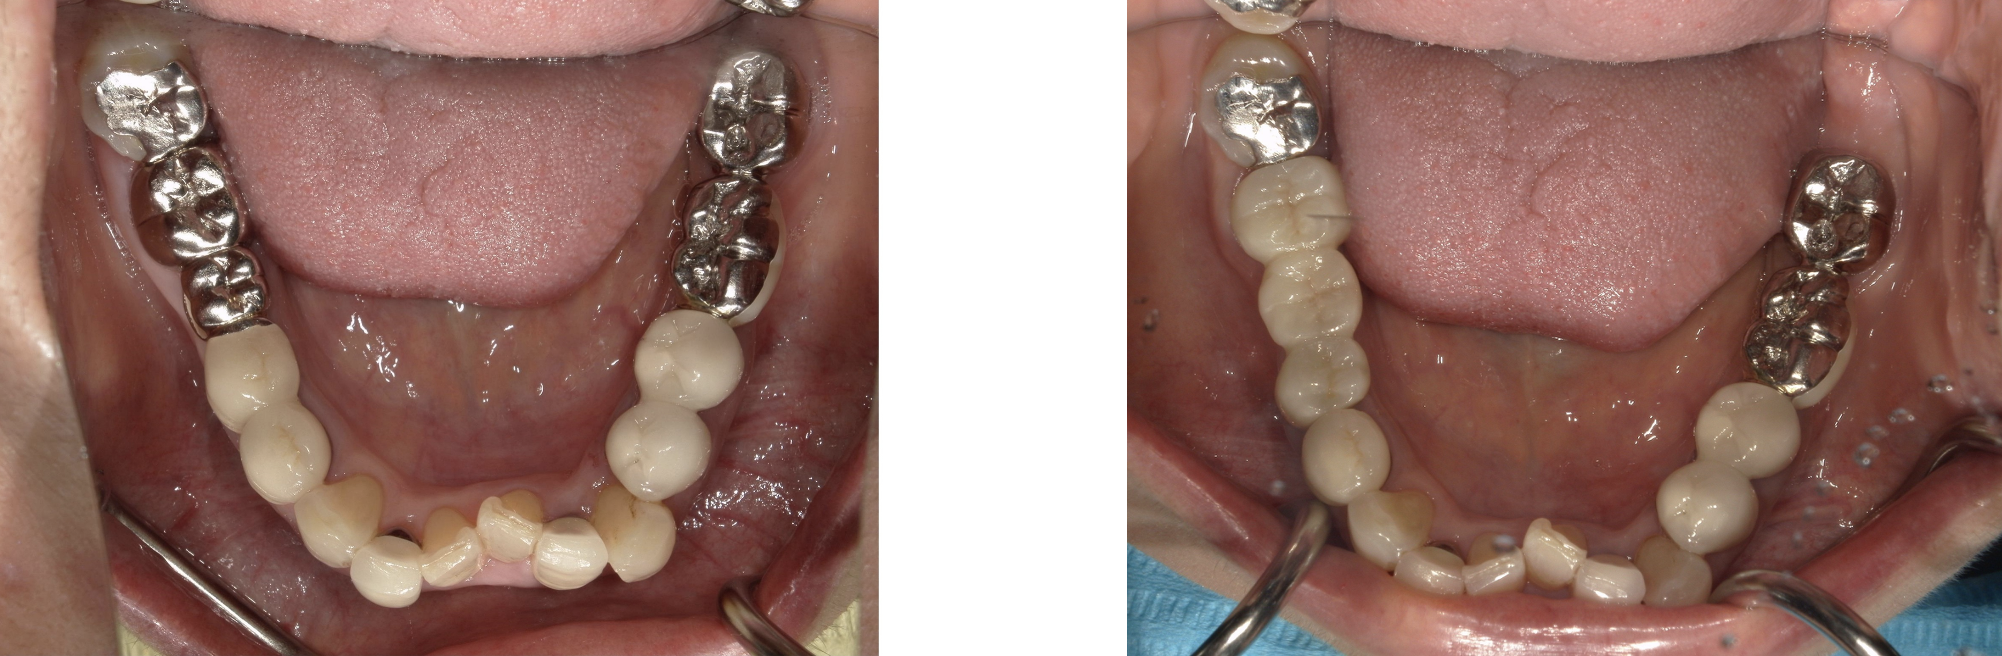

ジルコニアセラミックブリッジ 症例1

右下567番を金属ブリッジからジルコニアセラミックブリッジに変更した症例